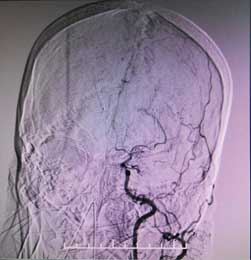

其实,大脑内的血管就像树木的树杈,主干的血液通过分支达到大脑的各个地方,但烟雾病人的主干是堵塞的。主干堵塞后,长出无数根毛细血管来替代,从血管造影上来看,如同烟囱里冒出的袅袅炊烟,因此被形象地称作烟雾病。

颅内烟雾状血管